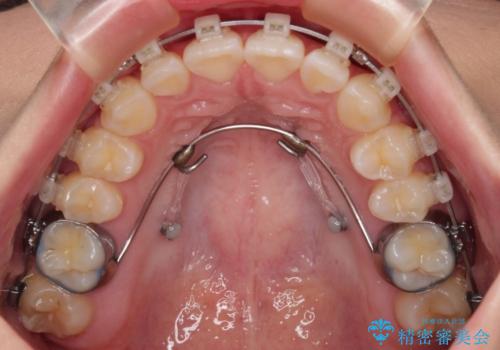

- 矯正装置

- 審美装置

抜歯するほどではないものの、やや口元の突出感が気になっていたので、補助装置により上顎臼歯を後方に移動させることで、突出感改善を図ることとしました。